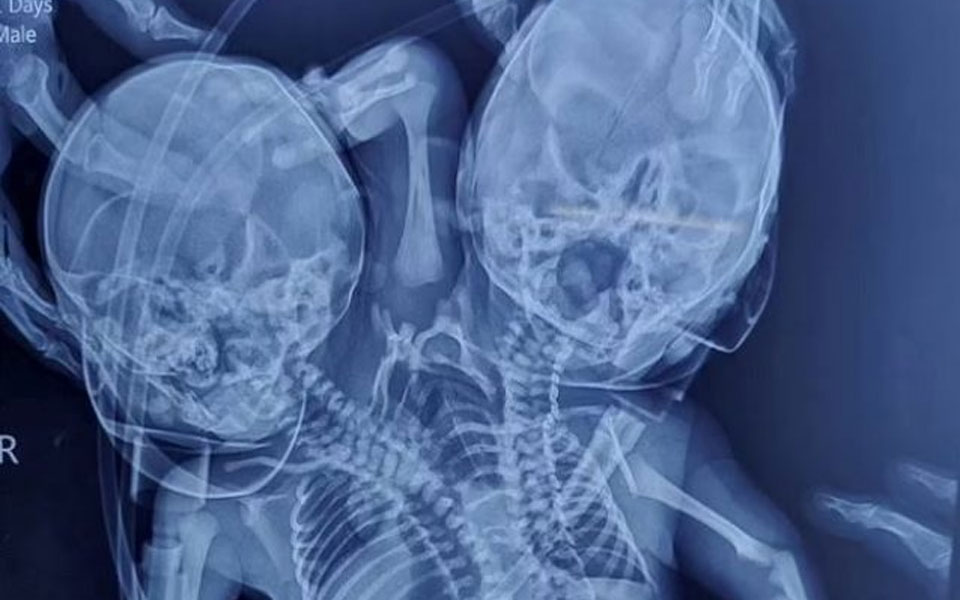

Ινδία: Γεννήθηκε μωρό με δύο κεφάλια, τρία χέρια και δύο καρδιές

«Τέτοιου είδους περιστατικά είναι σπάνια και η κατάσταση των μωρών παραμένει επικίνδυνη, ειδικά τις πρώτες μέρες», είπε ένας γιατρός για την υπόθεση.